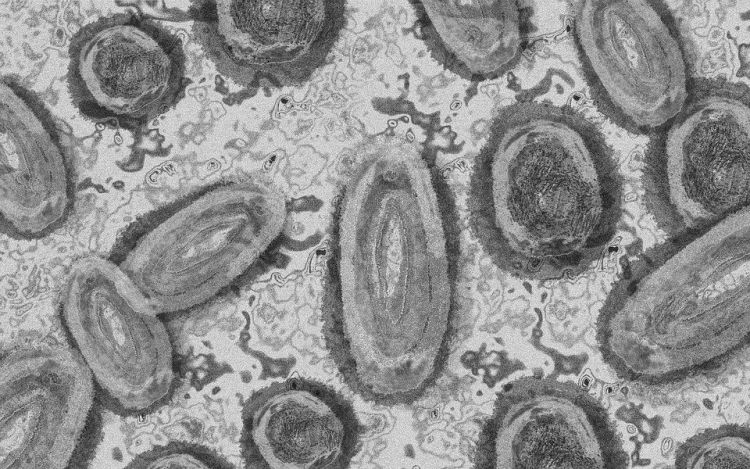

Belgiumban egy 3 év alatti gyermek fertőződött meg majomhimlővel - számolt be róla szerdán a Sudinfo hírportál.

Steven Van Gucht, a belga közegészségügyi intézet (Sciensano) fertőző betegségekkel foglalkozó osztályának vezetője azt nyilatkozta, hogy nagyon kivételes esetről van szó, a gyermeket valószínűleg saját szülei fertőzhették meg. Véleménye szerint nagyon ritka, hogy a fertőzés szülőről gyerekre terjed, de előfordulhat. Mint mondta, a gyermekek tünetei általában enyhék.

"A betegségben szenvedőknek nagyon kell vigyázniuk, hogy ne fertőzzék meg gyermekeiket. Akár egy törölközővel is át lehet adni a fertőzést" - magyarázta Marc Van Ranst virológus professzor a helyi sajtónak. Európában eddig 29 fertőzést igazoltak gyermekeknél.

Belgiumban a járvány kezdete óta 671 majomhimlős esetet regisztráltak a Sciensano kedden közzétett adatai szerint. 360 fertőzöttet Flandriában, 236-ot Brüsszelben és 75-öt Vallóniában jegyeztek fel, szinte minden érintett 16 és 71 év közötti férfi.

Harmincegy ember került eddig kórházba, egyikük sem szorult intenzív ellátásra. Halálos kimenetelű esetekről nem érkezett jelentés. A Sciensano tájékoztatása szerint a Belgiumban jelenleg rendelkezésre álló 3220 adag majomhimlő elleni oltóanyagból 1153 adagot használtak fel.

Stefaan Van der Borght, a járványkockázat-kezelési csoport (RMG) elnöke arra figyelmeztetett, hogy "a vakcina nem csodaszer," oltás után is fennáll a fertőzés veszélye. "Kerülni kell a betegségben szenvedő emberekkel való érintkezést, és korlátozni kell a szexuális kapcsolatot" - mondta.